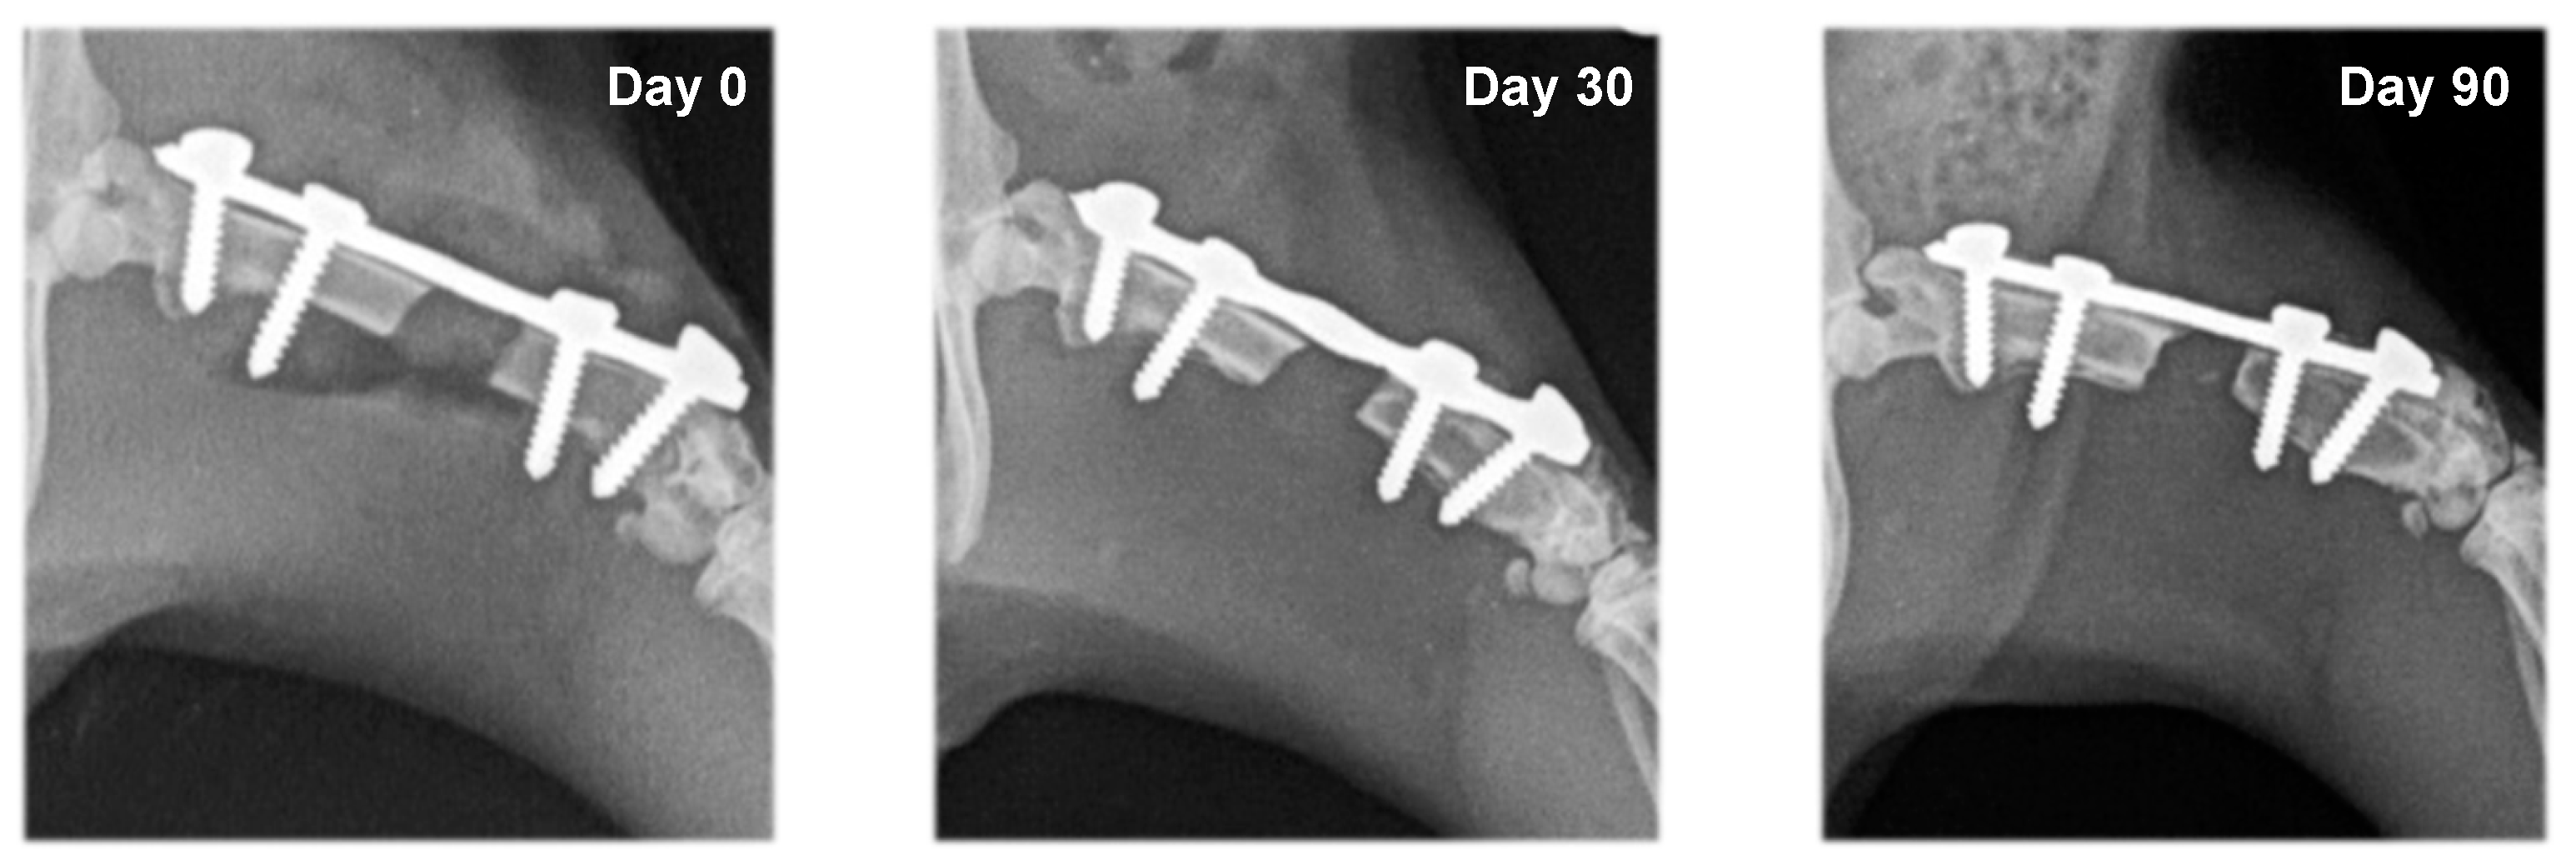

In rats from the control group (F1) and the group with systemic EPO application (F2), bone formation signs were not established. In the different study periods, osteotomy lines and the created segmental defects were clearly visible (Figure 3 and Figure 4).

Figure 3.

Serial craniocaudal radiographs of rat femurs from experimental group F1 on post-operative days 0, 30 and 90.

Figure 4.

Serial craniocaudal radiographs of rat femurs from experimental group F2 on post-operative days 0, 30 and 90.

The radiological bone healing scores, according to Oryan et al. (2015), in the different groups are presented in Table 1. In rats from the group with local EPO application (F4), bone formation was induced around the osteotomy margins, with statistically significant differences on post-operative days 30 and 90 vs. day zero. Compared to group F3 (collagen cone soaked with physiological saline), the difference of healing scores in group F4 by the 90th day was statistically significant (p < 0.05), which was associated with reduced bone defect size and the formation of bone bridges (Table 1).